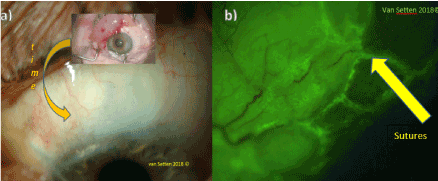

In the weeks following surgery, the initially visible fluorescein staining close to the sutures rapidly decreased. With decreases of size of the bleb also the staining does diminish remarkably during the first weeks of surgery (Figure 1).

Figure 1. a) Decrease of the elevation of the bleb after deep sclerectomy within a few weeks after surgery, b) Localized staining at the site of sutures after glaucoma surgery.